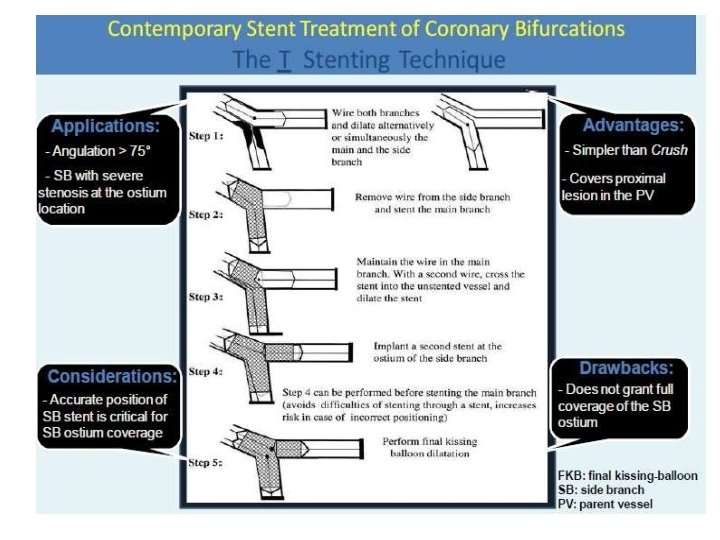

Stenting techniques 1)Provisional • Mainvessel stenting ± side branchangioplasty (Provisional) Tstenting, • TAP, • REVERSEINTERNAL CRUSH • REVERSECULOTTE. 2) elective • Culotte-stenting • Crush technique (reversecrush) T TECHNIQUE AND TAP • V STENTING • Y STENTING(SKS technique)

Modified T technique